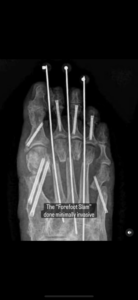

There is a lot of media these days about doing minimal incision bunion surgery, but patients should review our bunion and minimally invasive surgery services before choosing a procedure. Do not be a victim of the hardware doctor, and meet Dr. Singh to learn about his approach to true minimal incision correction. They think this is minimal incision. They make a small incision. Then they insert these large screws. Sometimes they insert screws and plates. This is not minimal incision. This is totally criminal. Who would want to have such a procedure done. Look at the second picture. This is a bunion. Who would want such correction done to them. Look at the third picture. How do you think the bunion is going to even heal? Stay away from the surgeons that profess minimal incision surgery using these types of hardware. Do yourself a favor and educate yourself.